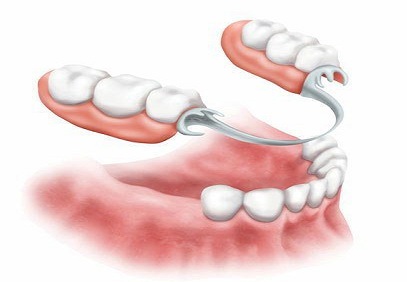

انواع پروتز پارسیل

پروتز متحرک پارسیل فلزی

پروتز متحرک پارسیل غیرفلزی

1. پارسیل اکریلیک – فلزی(Acrylic-metal parcel)

این دندان مصنوعی تکه ای از یک چارچوب فلزی و بخش دندانی تشکیل شده است. به دلیل استحکام و دوام بالای آن انتخاب مناسبی برای جایگزینی چند دندان از دست رفته است. این نوع پروتز پارسیل از ثبات بالایی برخوردار است.

2. پارسیل اکریلیک – سیمی (Acrylic parcel – wire)

دندان مصنوعی پارسیل سیمی که به آن پروتز پارسیل فریمی نیز می گویند، از یک چارچوب سیمی فلزی با گیره هایی برای ثبات، در اطراف دندان های باقی مانده استفاده میشود. این پروتز وزن سبکی دارد.